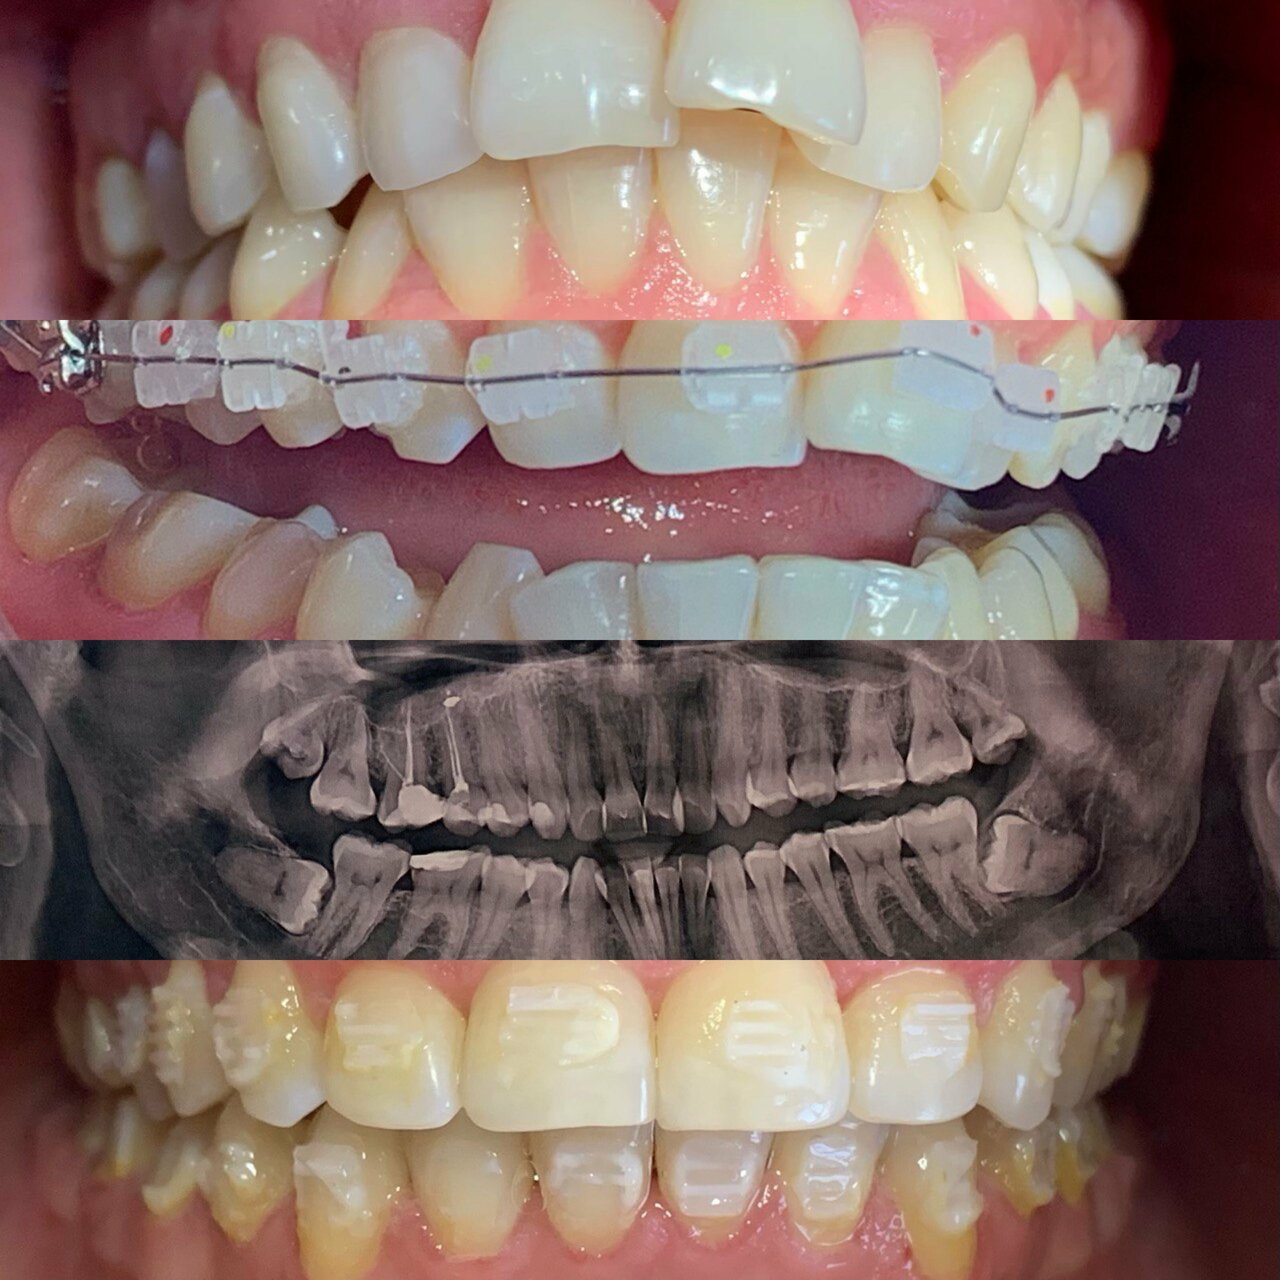

Основные направления работы включают общую стоматологию (лечение кариеса, удаление зубов, гигиену полости рта), ортодонтию (исправление прикуса, выравнивание зубов), хирургическую стоматологию (имплантацию, операции), эстетическую стоматологию (отбеливание, виниры, коронки) и детскую стоматологию.